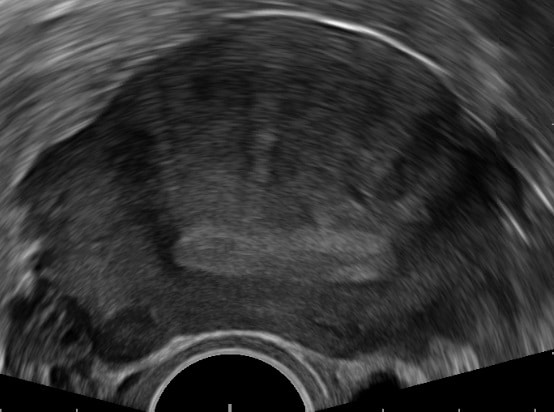

• Transvaginal ultrasound – highly observer-dependent, but there is agreement on the signs seen in adenomyosis.

• These include a globular uterine configuration, poor definition of the endometrial-myometrial interface, myometrial anterior-posterior asymmetry, intramyometrial cysts and a heterogeneous myometrial echo texture.

Fig 2

Adenomyosis identified on transvaginal ultrasound.